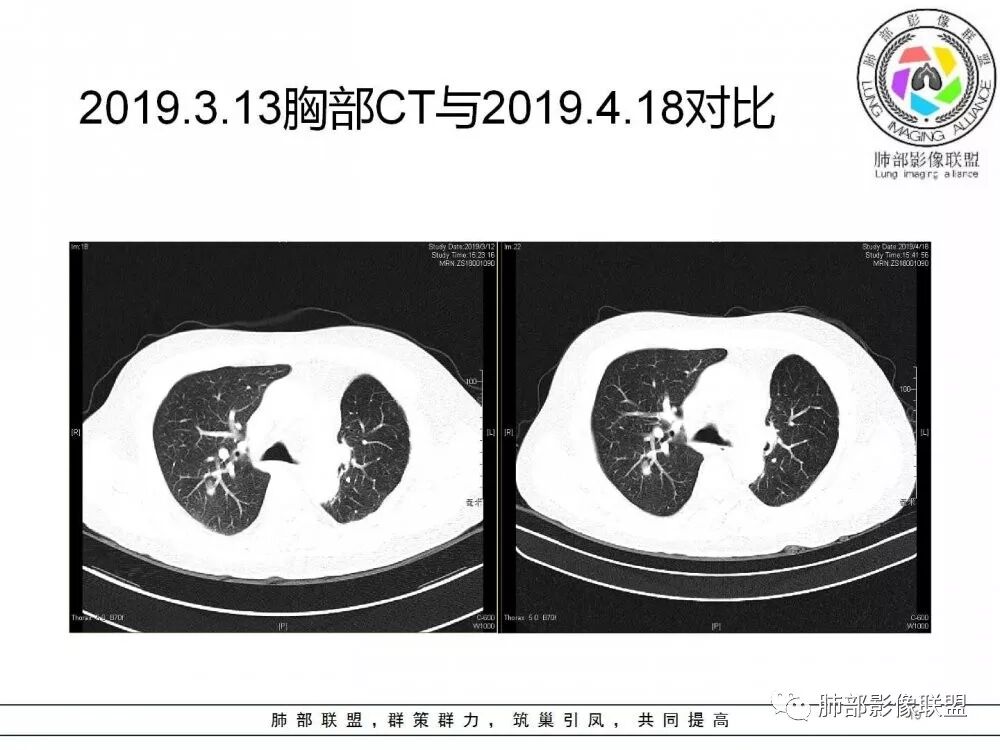

病灶从2月份就开始有,应该最早说是1月7号就有了,到3月13号稍微增大一点,到后面几乎没变化,到5月份好像稍微大一些,炎性应该是炎性,犹豫的是这个炎性到底什么病变呢?其实本没变化,它特点一个是在叶裂上,跟血管关系密切,但是病灶边缘稍收缩,病灶没有太大变化。

确实当时病人来了考虑转移可能,就测了基因,上了靶向药,两月变化不大